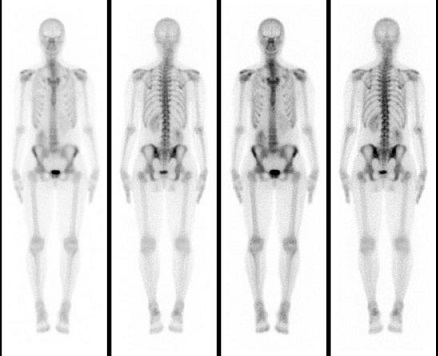

4- اسکن استخوانی Bone scan

به آن اسکن رادیوایزوتوپ هم میگویند. میتواند در مواردی مانند عفونت، سرطان، روماتیسم، اسپوندیلولیستزی و یا سایر علل به تشخیص کمک کند .